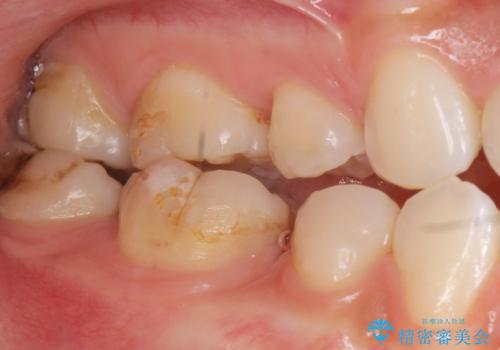

- 奥歯の隙間を治したいとご希望された患者様です。

学生時代に舌側矯正されていたものの、通院が大変になり治療を途中でやめてしまい、奥歯の間に隙間が残ってしまったそうです。

矯正せずに早く治したいという強いご希望とう蝕があることから、セラミッククラウンによる補綴治療で隙間を閉じることにしました。